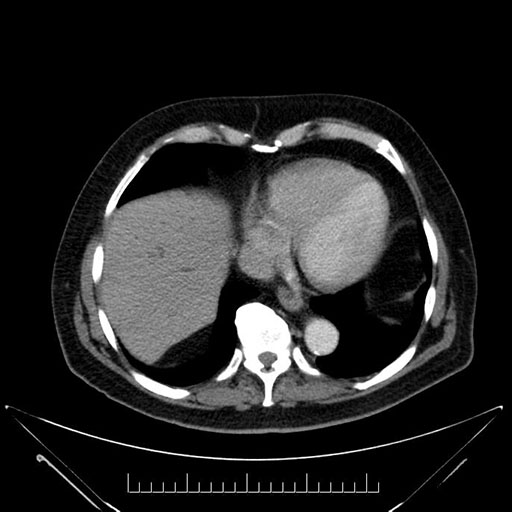

Whipple (pancreaticoduodenectomy) [case 7]

Imaging Analysis

Look through the patient's CT scan to identify any areas of concern for the necessary procedure.

Axial - 3 months prior